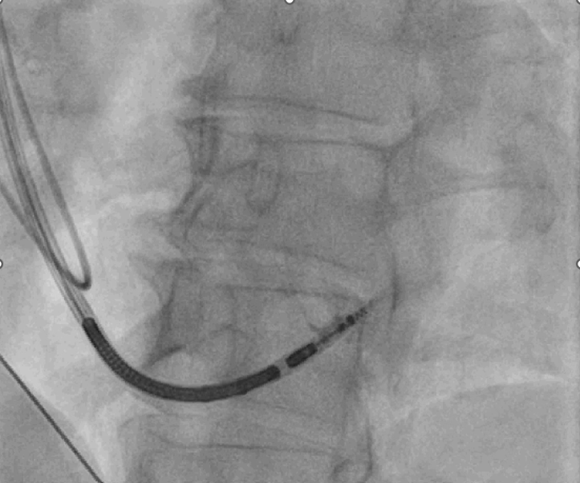

Es erfolgte die Indikationsstellung zum ICD. Aufgrund des AV-Blocks I° (PQ 360ms) und eines erneuten kardioversionspflichtigen Vorhofflimmerns wurde mit der Patientin über die Art der ICD-Implantation diskutiert. Ein extrathorakales und transvenöses 1K-System wurde bei zu erwartendem Stimulationsbedarf nicht in die engere Wahl genommen. Bei derzeit noch normaler Pumpfunktion aber hohem Risiko für die Entwicklung einer stimulationsbedingten Kardiomyopathie entschieden wir uns für ein transvenöses 2K-LBBAP- ICD-System (Bild 5-7).

Interoperative KM-Darstellung

Bild 6: LAO 30°, Intraoperative KM-Darstellung über die CSP-Schleuse in Septalposition mit eingeführter Single Coil ICD-Elektrode und bereits herausgedrehter Schraube.